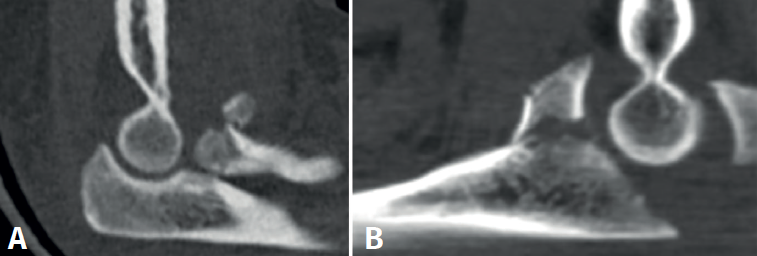

- Tomografía axial computarizada (TAC): en especial la reconstrucción 3D, que nos permite evaluar con detalle las fracturas. En el caso de la cabeza radial, su extensión y conminución, y en cuanto a la apófisis coronoides, su tamaño. De esta manera, la TAC permite una adecuada planificación preoperatoria, decidiendo aspectos como el abordaje o el tipo de osteosíntesis(7)(Figura 2).